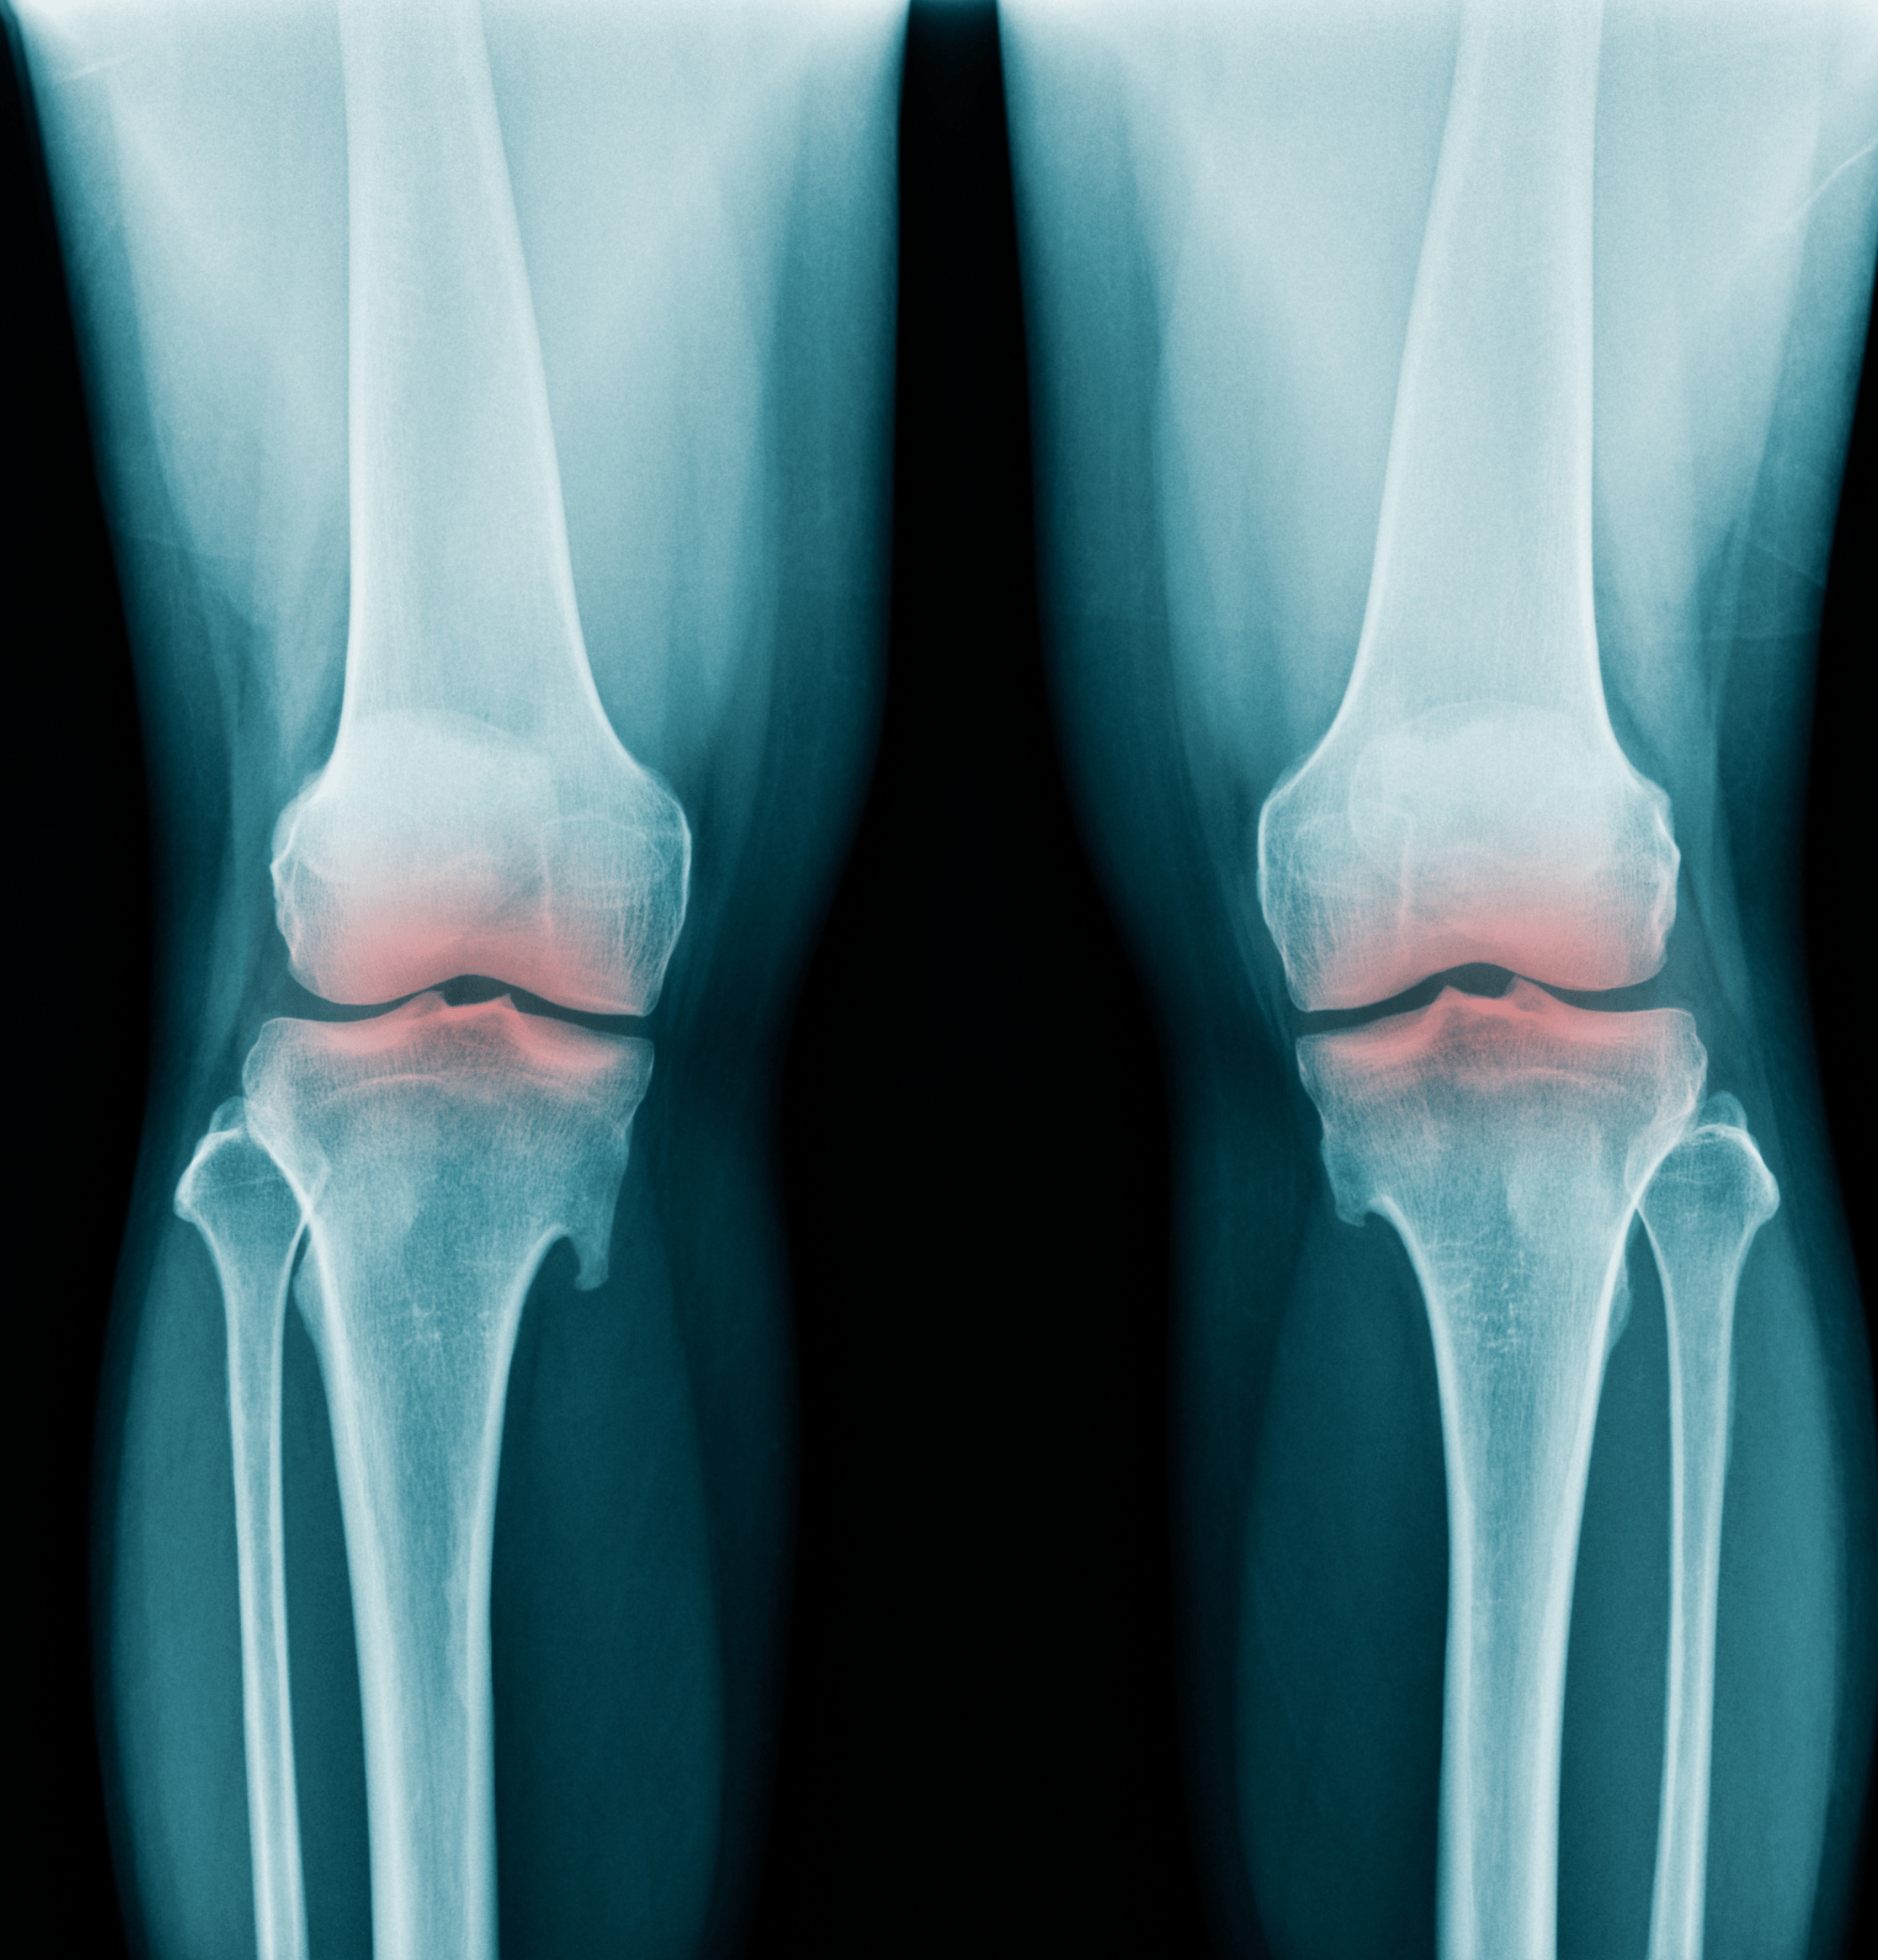

A cosa serve la Radiografia del Ginocchio?

La radiografia del ginocchio viene utilizzata per diagnosticare una varietà di condizioni che colpiscono l'articolazione, tra cui:

Fratture o lussazioni: Identificare fratture ossee o dislocazioni dell'articolazione.

Escludere la presenza di infezioni o masse tumorali nell'area del ginocchio.

Artrite: Valutare segni di infiammazione e degenerazione articolare.

Indagare danni ai menischi, che sono strutture di cartilagine che ammortizzano l'articolazione.